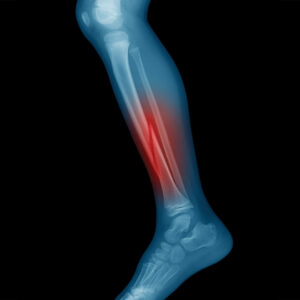

If you’re suffering from a stress fracture, seek treatment. During your appointment, your orthopedist will do a thorough physical exam to look for limping and other gait issues, tenderness, swelling, discoloration, or pain. Your orthopedist will also perform several muscle tests and impact maneuvers.

If a bone stress injury is suspected, your orthopedist will begin by recommending an X-ray. However, sometimes stress fractures are so thin they might not appear. If that’s the case, your orthopedist might recommend further diagnostic imaging, such as magnetic resonance imaging (MRI), which can provide a more detailed image. Once your orthopedist has diagnosed your injury, they’ll work with you to create a treatment plan tailored toward you and your goals.